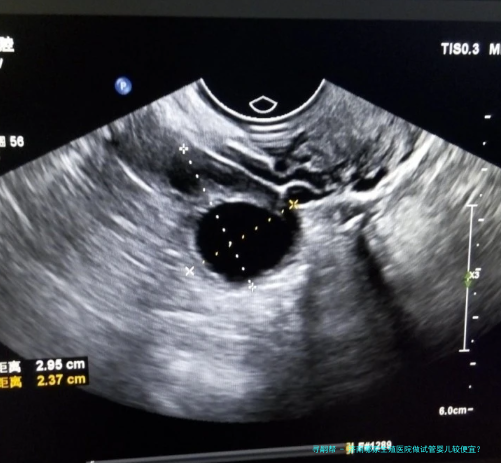

诊断费:对于试管婴儿技术,起首需要进行诊断,以认定病患是不是适合进行试管婴儿技术,病人的生殖系统肿瘤、妊娠合并症等情况,所以诊断费是必不可少量的。一般来说诊断费用约为一千元左右。检查费:检查费包括试管婴儿助孕技术评介、腹腔镜检查、辅助生殖技术检查等,一般情况下,检查费用约为2000元左右。药物费:在试管婴儿技术过程当中,需要适当的药物支持,多见的药物费用有激素费、人工受精费、着床技术费等,一般情况下,药物费用约为3000元左右。医疗费:医疗费主要包括试管婴儿技术手术费用及精子搜集费用等,正常情况下,医疗费用约为5000元左右。住院费:如果需要实行住院手术,依旧要支付住院费用,正常情况下,住院费用约为3000元左右。孕检费:试管婴儿技术完成后,须要定期进行孕检,以确定胎儿是否是生长正常,通常情况下,孕检费用约为2000元左右。